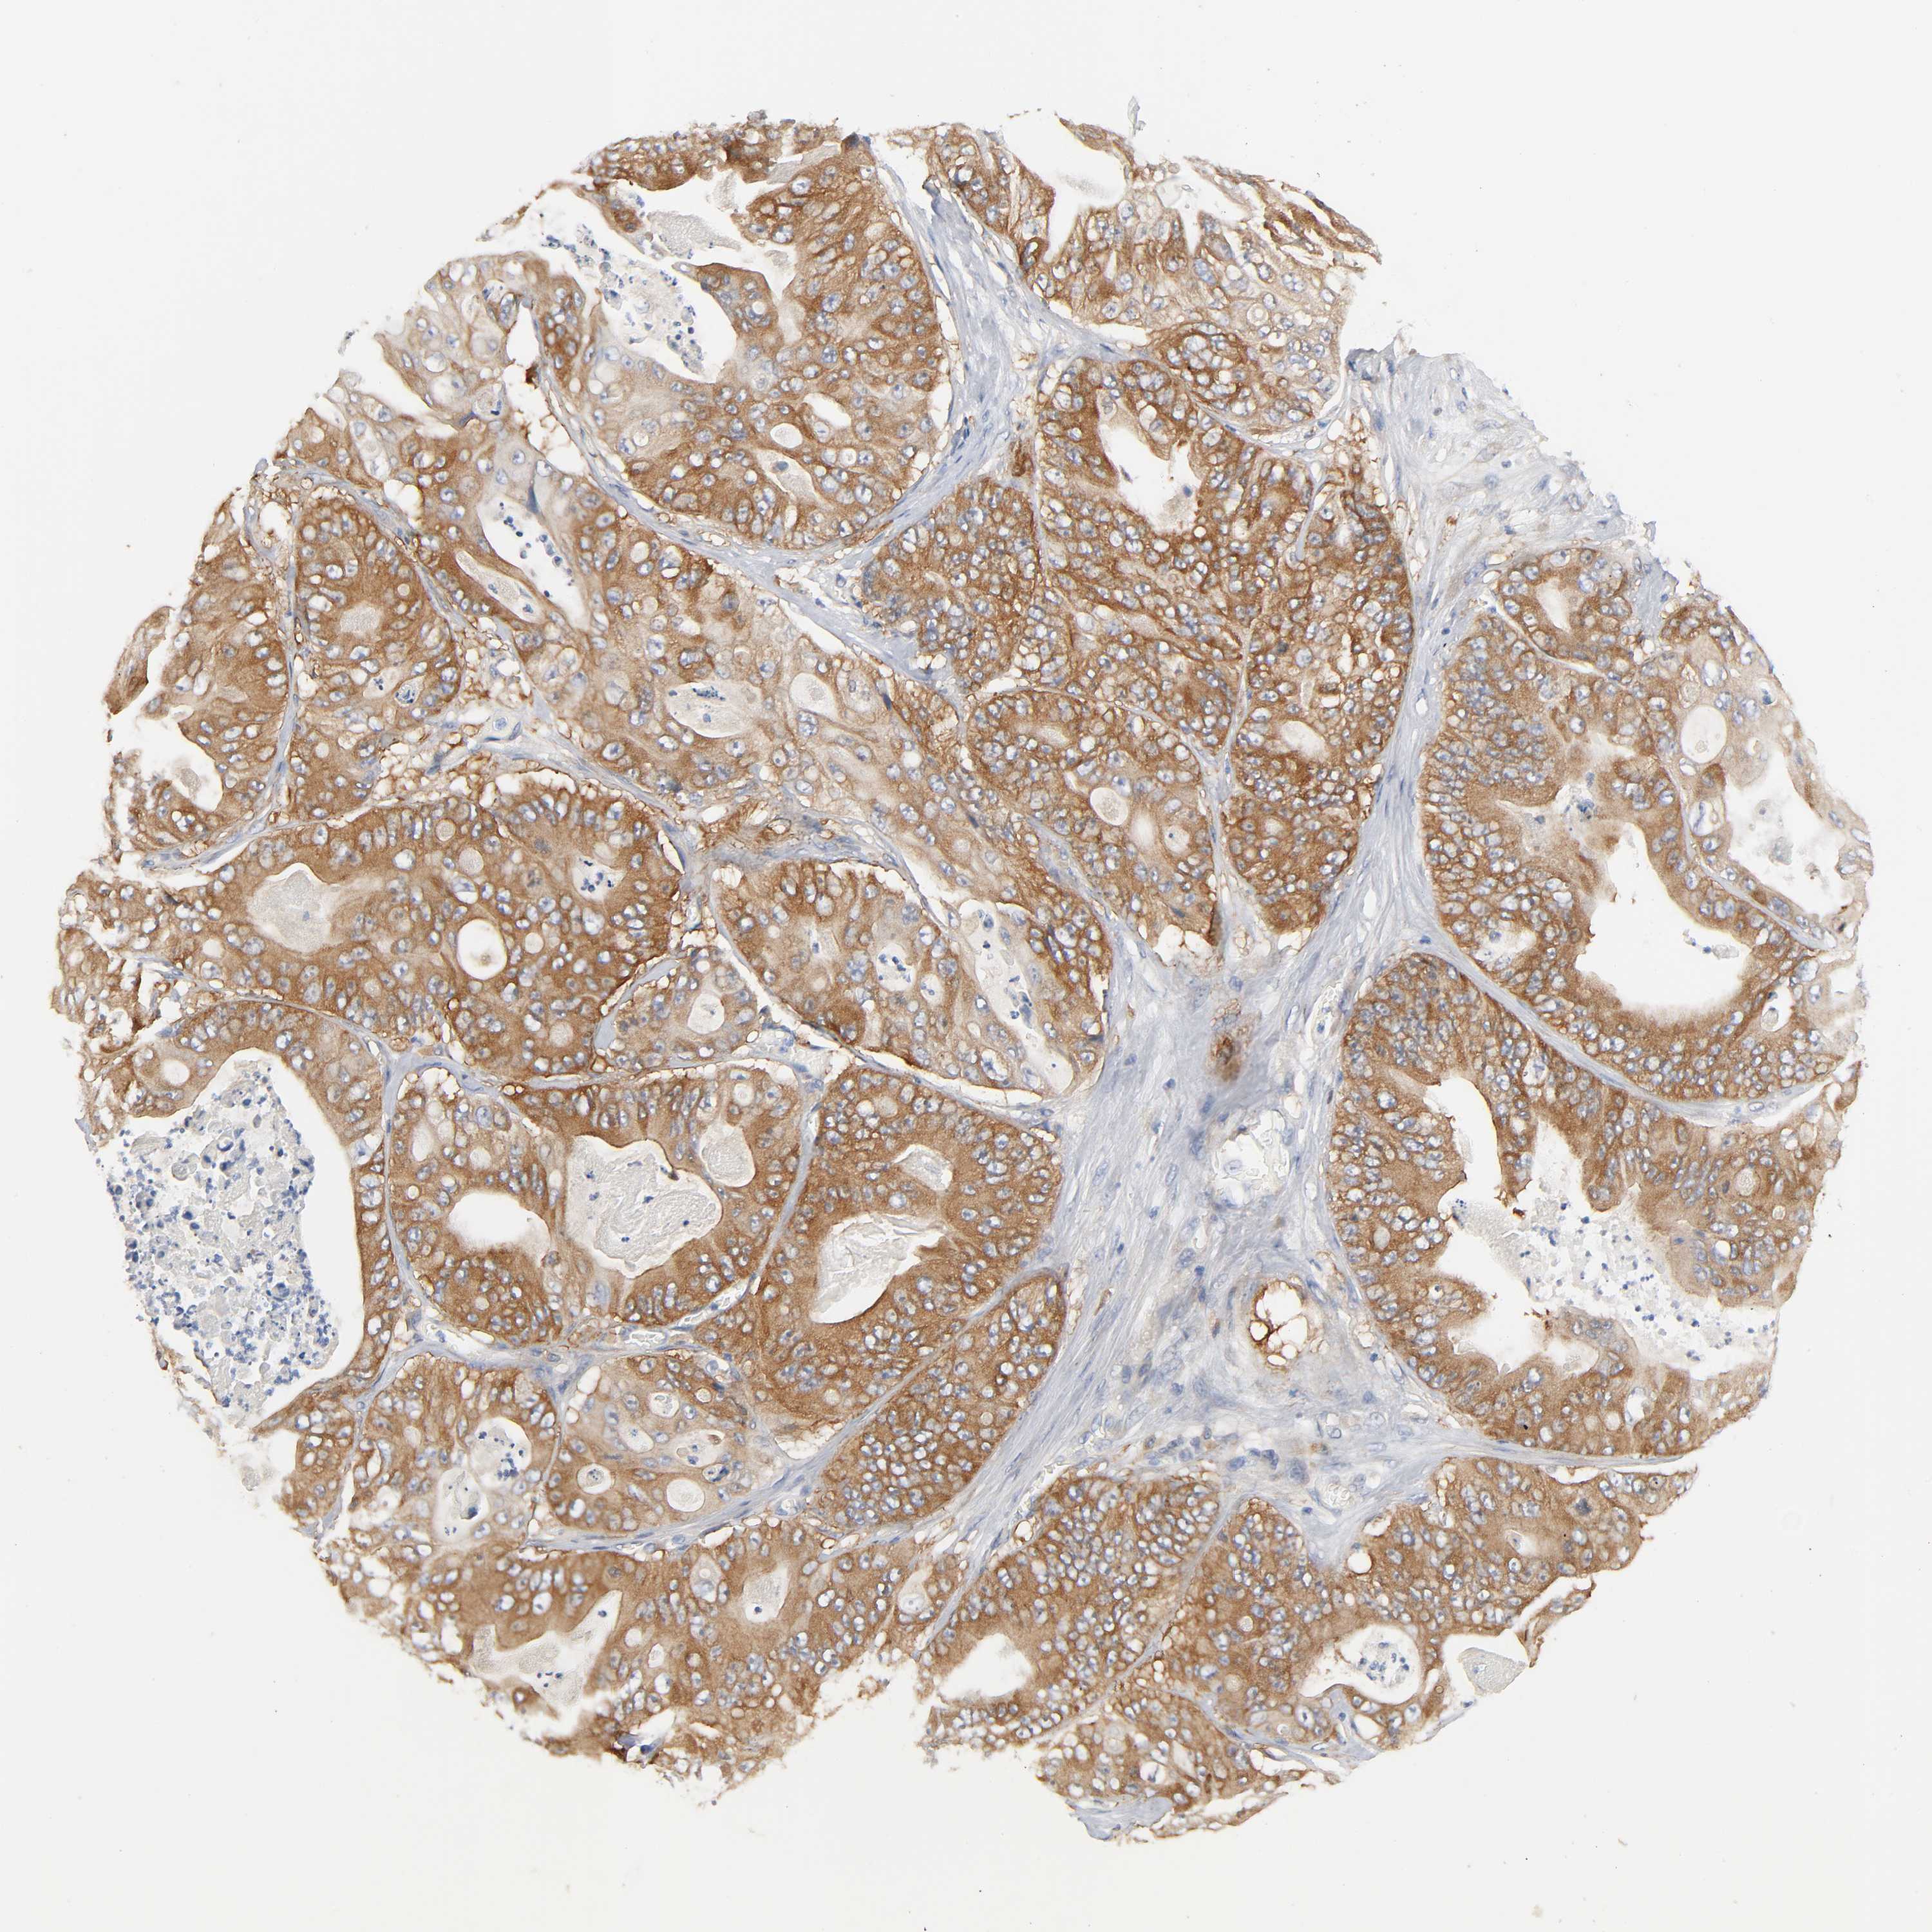

STOMACH CANCER - Protein expressioni

A mouse-over function shows sample information and annotation data. Click on an image to view it in a full screen mode. Samples can be filtered based on level of antibody staining by selecting one or several of the following categories: high, medium, low and not detected. The assay and annotation is described here.

Note that samples used for immunohistochemistry by the Human Protein Atlas do not correspond to samples in the TCGA dataset.

Antibody stainingi

Antibody staining in the annotated cell types in the current human tissue is reported as not detected, low, medium, or high, based on conventional immunohistochemistry profiling in selected tissues. This score is based on the combination of the staining intensity and fraction of stained cells.

Each image is clickable and will lead to virtual microscopy that enables deeper exploration of all samples and also displays staining intensity scores, fraction scores and subcellular localization as well as patient and tissue information for each sample.

Antibody HPA003894

Antibody HPA005437

Antibody CAB001945

Staining

High

Medium

Low

Not detected

Adenocarcinoma, NOS

Adenocarcinoma, High grade